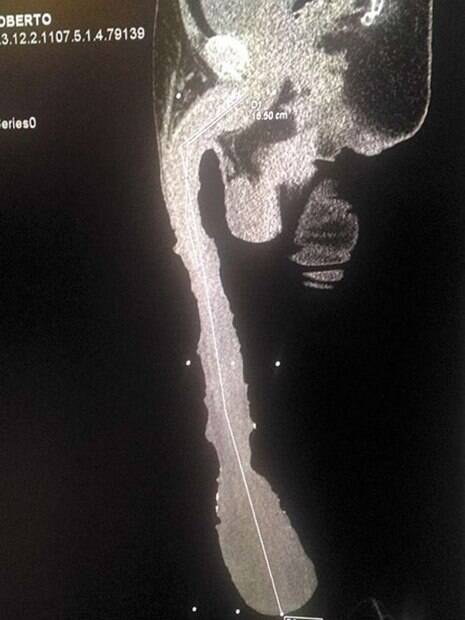

De fato, ele conseguiu atingir a marca de 48 centímetros de pênis, mas, nessa idade em que ele está, o membro é apenas um problema em sua vida.

Os médicos já realizaram exames no órgão de Roberto e notaram que mais da metade de seu pênis é composto por prepúcio e vasos sanguíneos. As glândulas penianas dele esticam somente 17,78 centímetros.